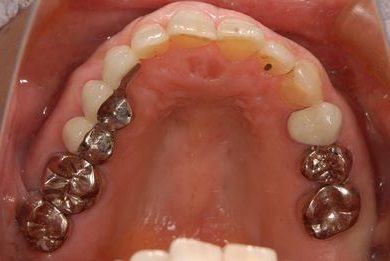

主訴 噛むと痛い。(咬合痛がある)

治療前

• 治療前